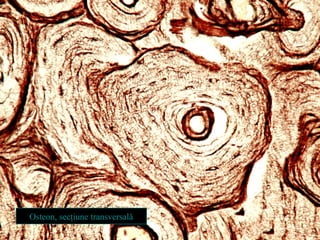

Sistemul Havers osteonul

• Unitatea morfofuncţională a

osului lamelar

• Paralel cu axul mare al

osului

• Formă cilindrică (de

coloană)

• Componente

 Lamele osoase concentrice

 Canal osteonal, cu ţesut

conjunctiv şi vase sanguine

 Canalele osteoanelor vecine

sunt interconectate prin

canale oblice (Volkmann)

Osteon, secţiune transversală

Dispoziţia concentrică a lamelelor osoase